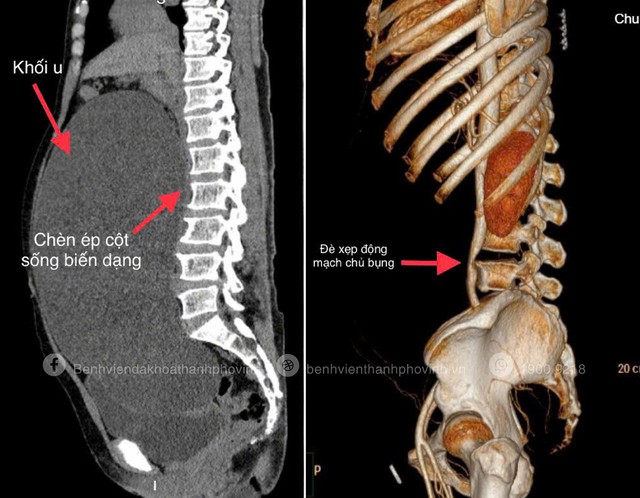

Image of a giant ovarian cyst occupying the entire abdomen, compressing and causing abdominal aorta collapse, organs being displaced, and ureters being compressed, causing bilateral renal pelvis dilation.

Here, the doctors were surprised to see the patient's abdomen swollen and tense like that of an 8-month pregnant woman. The 256-slice CT scan showed a giant ovarian cyst occupying almost the entire abdomen, compressing and collapsing the abdominal aorta, displacing many organs, compressing the ureters, causing dilation of the renal pelvis on both sides, and even deforming the spine.